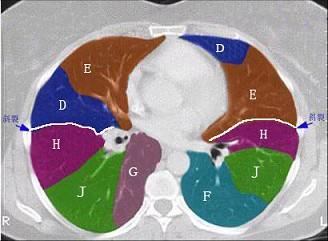

结合肺段模式肺动脉干与右肺动脉层面(如图),选出右肺中叶的组成 ( )A.BB.B+CC.B+C+DD.D+EE.D+E+F

问题 结合肺段模式肺动脉干与右肺动脉层面(如图),选出右肺中叶的组成 ( )

选项 A.B B.B+C C.B+C+D D.D+E E.D+E+F

答案 D